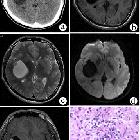

Three cases

of sporadic meningioangiomatosis with different imaging appearances: case report and review of the literature. Solid meningioangiomatosis. (a) CT scan showed an irregular mixed high-density mass in the left middle cranial fossa. (b) On T1WI, the lesion demonstrated low and equal signal intensity. (c) On T2WI, the lesion showed high signal intensity with a multiple flow void effect. (d) On post-contrast MRI, the lesion showed significant and homogeneous enhancement. (e, f) Microphotography of specimens showed extensive fibroblastic proliferation and an increased number of vessels surrounded by meningothelial cells.

of sporadic meningioangiomatosis with different imaging appearances: case report and review of the literature. Cystic meningioangiomatosis with a cystic-mural nodule pattern. (a) CT scan showed a cystic-mural nodule lesion in the right insular lobe. (b-d) In non-enhanced MRI, the cystic content demonstrated similar signal intensity as cerebrospinal fluid (CSF), while the mural nodule demonstrated iso-signal intensity on T1WI, T2WI, and DWI. (e) On post-contrast MRI, the mural nodule demonstrated significant enhancement, while the cystic wall and content showed no enhancement. (f) Pathological examination showed perivascular spindle-cell proliferation.

of sporadic meningioangiomatosis with different imaging appearances: case report and review of the literature. Cystic meningioangiomatosis with a multiple microcystic pattern. (a, b) DWI and T2WI demonstrated a low signal intensity nodule in the left parietal cortex and multiple small cysts surrounding it. (c) On post-contrast MRI, the nodule was remarkably enhanced. (d) Microscopically, fibroblast-like spindle cells were arranged in a spiral shape around multiple vessels, and the cortical neurons were entrapped within the lesion.